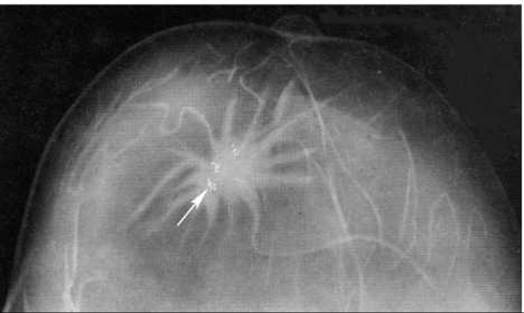

Рак молочної залози на мамограмі виявляється у вигляді тіні округлої форми і доволі рівними контурами при експансивному типі росту, або у вигляді тіні неправильної форми (зірчастої чи амебоподібної), з нерівними нечіткими контурами, неоднорідної структури - при інфільтративному типі росту. Важливою діагностичною ознакою є наявність мікрокальцинатів, які супроводжують злоякісну пухлину в 50% випадків і утворюються в ділянках некрозу пухлини (мал. 273). Додатковими рентгенознаками раку є: 1) порушення симетрії залоз; 2) втягнутість і потовщення шкіри; 3) втягнутість соска; 4) локальне потовщення протоків і подовження їх видимості до соска («ракова доріжка») внаслідок розростання пухлини вздовж протоків (мал. 274); 5) збільшення пахвових лімфовузлів; 6) поява групи дрібних судин, що живлять пухлину (мал. 275). Навколо злоякісної пухлини може виявлятись широкий обідок просвітлення, обумовлений набряком в ділянці пухлини; при цьому рентгенолог пальпує більше утворення, ніж на рентгенограмі.

Мал. 275. Рак молочної залози на мамограмі. Нові судини позначені стрілкою.